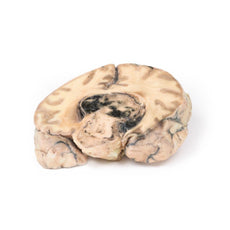

3D Printed Astrocytoma

Clinical History

A 73-year-old female was admitted with new left-sided hemiplegia. On further questioning she

revealed a 3-month history of headaches, nausea and deteriorating balance. CT brain revealed an inoperable brain

tumour. She died 1 week after being admitted.

Pathology

This brain specimen is a coronal section. In the right temporal lobe, a poorly demarcated tumour is

present. There is enlargement of the hemispheres and flattening of the gyral pattern. From the posterior aspect

of the specimen subfalcine herniation* is appreciated and the tumour appear less well differentiated with

haemorrhagic and necrotic foci. Histology of this tumour showed an astrocytoma, Grade III/IV.

*In subfalcine

(or cingulate) herniation, the most common type of brain herniation, the innermost part of the frontal lobe is

pushed under part of the falx cerebri, between the two hemispheres of the brain.